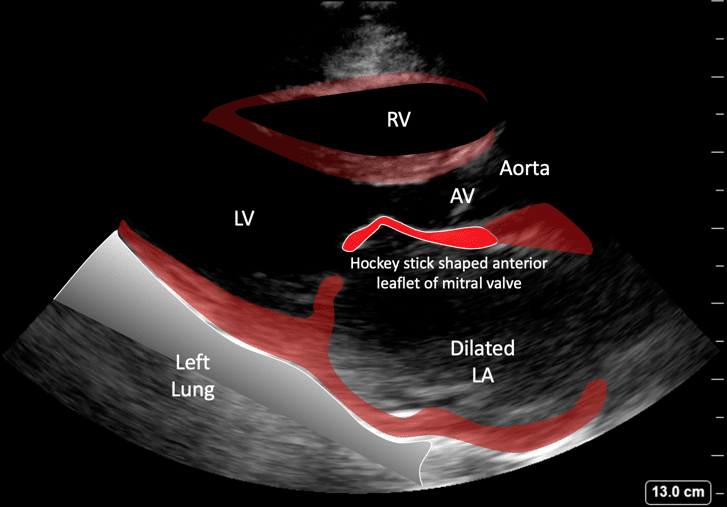

Hockey Stick Sign Mitral Stenosis . Echocardiography is used is used to establish the anatomy of the valve, confirming a typical “rheumatic” or “hockey stick” appearance. These morphological and functional characteristics suggested mitral rheumatic disease. Stenosis severity is determined in 3 ways. Patients with cn < 4 mm hg/ml may remain symptomatic after successful valvuloplasty. And the posterior mitral leaflet (pml) has. Low nunes scores correctly predict good outcomes even when wilkins scores are >8. The maximal amplitude of motion occurs in the mobile midsection, giving the anterior mitral leaflet an arched appearance, convex toward the lv outflow tract in diastole. Decreased ejection fraction in mitral stenosis is caused by reduced preload.